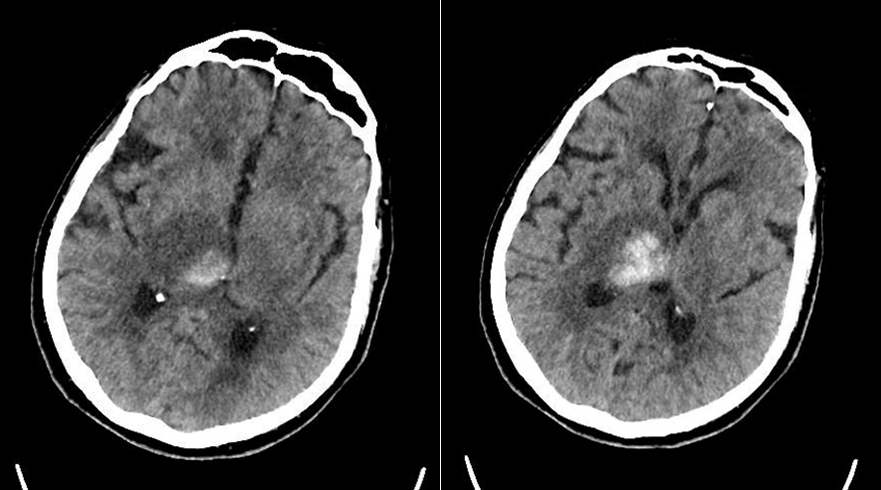

Le type d’hémianopsie est très important car il permet de localiser une atteinte neurologique, en connaissant le trajet des voies optiques.

Cette question supposait d’avoir bien en tête le schéma des voies optiques, et d’avoir des repères sur les principaux territoires vasculaires cérébraux et l’atteinte clinique associée. Il bien mentionné par le CEN que l’hémianopsie latérale homonyme gauche peut se voir dans un AVC sylvien superficiel droit.

Tableau d’après le Collège des enseignants de neurologie. Altération aiguë de la vision.